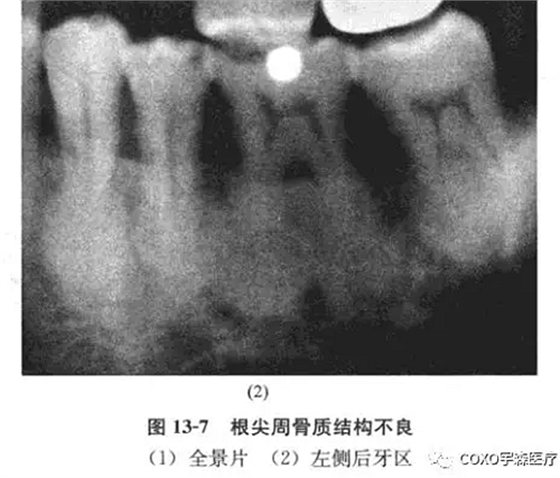

病例: 男性,71歲,雙側(cè)下頜骨后牙區(qū)反復(fù)腫脹2年余,曾在當(dāng)?shù)蒯t(yī)院口腔科行5]根管治療術(shù),效果不明顯,而將5]拔除,拔牙創(chuàng)一直未愈并伴疼痛,故轉(zhuǎn)我院就診。

x線片示:雙側(cè)后牙區(qū)高密度陰影(圖13-7),初步診斷:雙側(cè)后牙區(qū)根尖周骨質(zhì)結(jié)構(gòu)異常,伴感染,收入院。

全麻再加局麻,拔除64-45 64]牙根肥大,成骨樣物質(zhì),[45根尖肥大,有牙骨質(zhì)樣物質(zhì),[4拔牙創(chuàng)有膿液。64-45之拔牙創(chuàng)刮治,氯霉素沖洗,置碘仿紗條,縫合。病理診斷:雙側(cè)上下頜骨根尖周牙骨質(zhì)增生,拔牙創(chuàng)炎性肉芽組織,伴表面上皮增生。

根尖周炎與根尖周牙骨質(zhì)結(jié)構(gòu)不良的主要鑒別是前者為牙髓炎性壞死引起,而后者的演變有一個有趣的過程, 線片表現(xiàn)出三個不同時期,無論何期牙髓均為活髓,根尖周病變中鈣化物可能完全是牙骨質(zhì),也可能為骨質(zhì),或二者皆有。

其演變過程:正常牙槽骨-纖維變性-致密的、非典型的再礦化。

初期階段(纖維變性或溶骨階段)其特征是根尖牙周間隙中成纖維細(xì)胞和膠原纖維增生,造成硬骨板及其周圍的松質(zhì)骨吸收(圖13-8),不同于根尖周炎或根尖周囊腫,新生物是無炎癥的,神經(jīng)和血管在根管的進(jìn)出是無影響的。

中期(早期的根尖周牙骨質(zhì)結(jié)構(gòu)不良)大多數(shù)在活髓牙的根端,表現(xiàn)為孤立性病變或多發(fā)性病變,通常無自覺癥狀,極少數(shù)顯示輕度頜骨膨脹,x線片上顯示鈣化灶時,可認(rèn)為病變是成熟的中間期,隨著鈣化成分逐漸增多及出現(xiàn)融合,病變的密度亦增高,不同病變及不同患者間鈣化灶的大小、形狀、數(shù)目等變化較大,不引起牙根吸收。

晚期(成熟的根尖周牙骨質(zhì)結(jié)構(gòu)不良)病變在活髓牙根端,孤立或多發(fā)性,x線片密度高,影像均勻一致,大多數(shù)為圓形或卵圓形,但偶爾為不規(guī)則形,組織學(xué)上幾乎完全由不同比例的致密牙骨質(zhì)和骨組織形成,腔隙或血管間隙很少。

筆者所報道之病例,根尖周牙骨質(zhì)結(jié)構(gòu)不良的表現(xiàn)各階段都有,但以成熟階段為主,牙根已變成圓形或橢圓形,有時,病變擴(kuò)大,致密質(zhì)骨膨脹,粘膜潰爛,繼發(fā)感染,也可逆行性引起牙髓炎癥、甚至壞死,該患者就出現(xiàn)過因牙痛就診行根管治療術(shù)的經(jīng)歷。